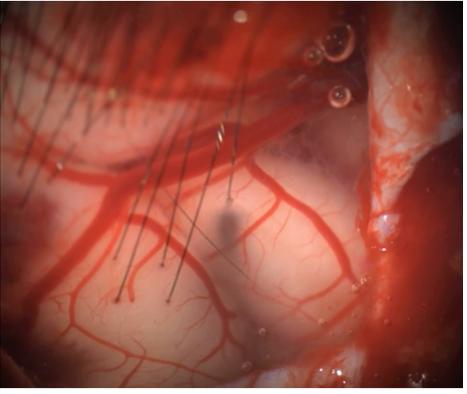

马斯克搞的就是侵入式,需要把颅骨开个洞,上面这些黑丝就是植入的电机,红色的是脑内的血管。

它能实现的功能和传输效率都超过非侵入式,因为理论上放置得离神经元越近,能获得的信息清晰度就越高,但很显然这样存在安全风险和伦理要求。